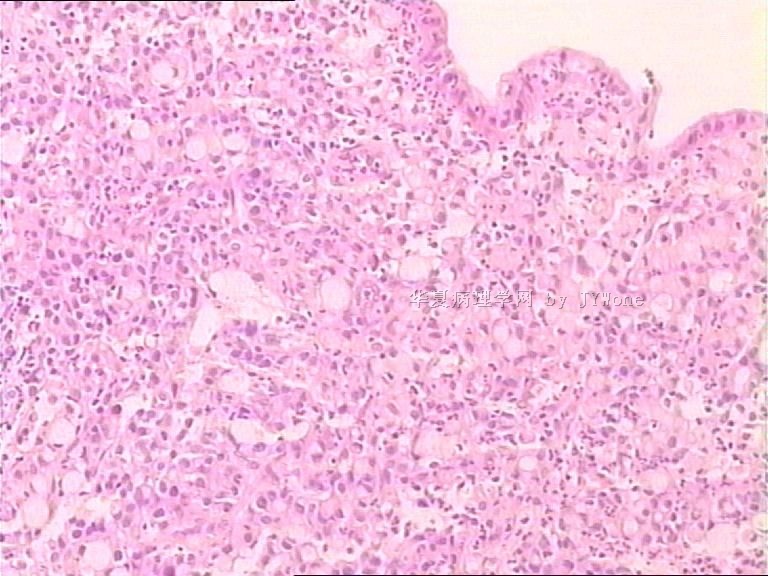

肾脓肿细胞图描述,肾脓肿切片图片描述

肾脓肿

肾脓肿切片图片描述

肾脓肿镜下图片

肾脓肿切片图片

肾脓肿切片